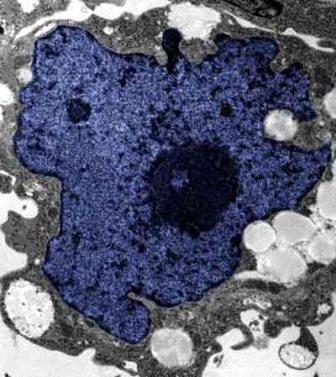

在成人體內(nèi)及胚胎內(nèi)發(fā)現(xiàn)的干細(xì)胞屬于主細(xì)胞,能發(fā)育成各種各樣的組織,可作為人體“修補(bǔ)工具箱”,取代死去及腐壞細(xì)胞組織。此前,最可行的干細(xì)胞為胚胎干細(xì)胞,但它的使用一直受到爭(zhēng)議,因?yàn)橐谂咛コ槿「杉?xì)胞會(huì)令胚胎死亡,有人認(rèn)為這樣是變相奪走一條生命。

2007年,日本京都大學(xué)教授山中伸彌為首的科研小組證明,利用病毒倒撥普通皮膚細(xì)胞的“生理時(shí)鐘”,可把它們變成像胚胎干細(xì)胞那樣具備“變身”能力的細(xì)胞。但利用病毒把基因輸入細(xì)胞,有可能導(dǎo)致癌癥。這即是說使用這些細(xì)胞的風(fēng)險(xiǎn)很大。

來自英國(guó)和加拿大的兩組研究員所用的新方法不必使用病毒。這項(xiàng)新突破暗示科學(xué)家現(xiàn)在能更認(rèn)真地看待在醫(yī)學(xué)中利用皮膚干細(xì)胞(即誘導(dǎo)多功能干細(xì)胞,俗稱“iPs”細(xì)胞)的前景。

這些細(xì)胞只要配以適當(dāng)?shù)幕瘜W(xué)品和蛋白質(zhì),就能轉(zhuǎn)化成腦神經(jīng)元、制造胰島素的胰腺細(xì)胞、骨或軟骨、心臟肌肉,或其它多種組織。這些細(xì)胞利用病人皮膚來培育,更暗示它們不會(huì)被人體排斥。